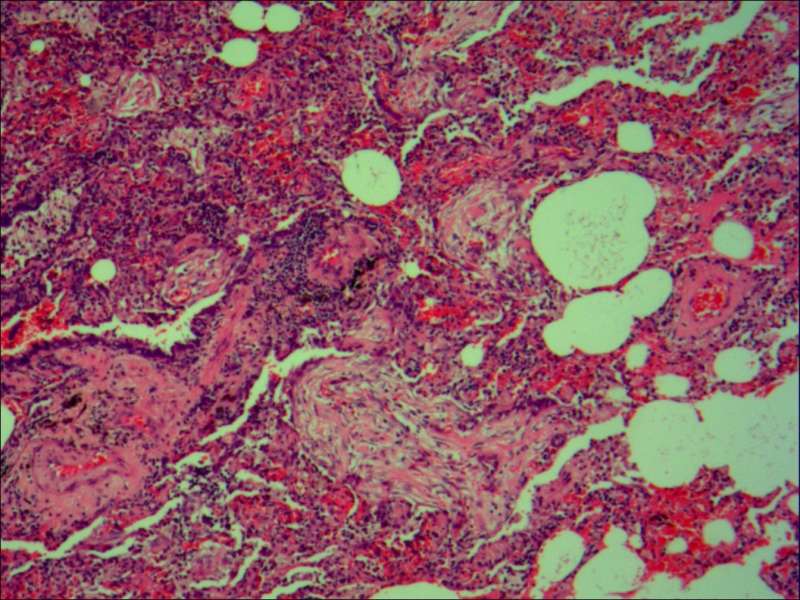

最后发一例化脓性炎症

中性粒细胞很多,此处组织结构破坏

左侧液化,脓肿壁较规则平滑

周围的炎症机化区

破坏力在这里逐渐减弱

逐渐从中性粒细胞转为淋巴细胞为主